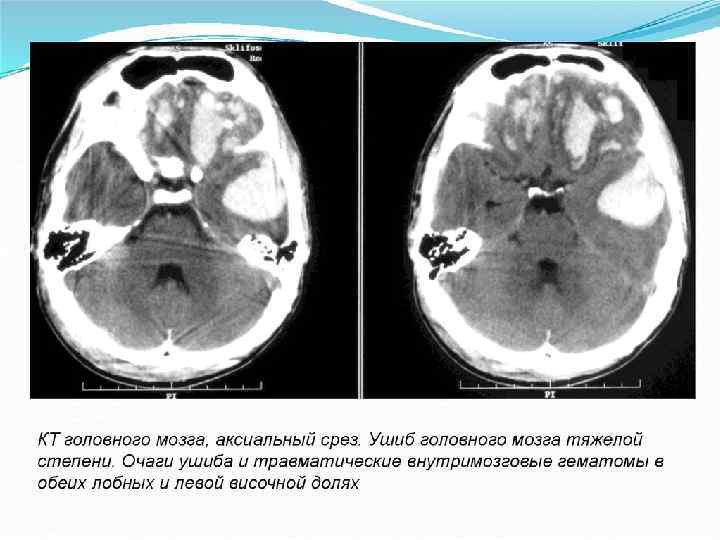

Люмбальдық тесу арқылы алынған ми-жұлын сұйығы қанмен боялады. КТ-да мидың мылжалануынан әр текті тығыздықтағы бөліктер анықталады. Бұлар, біртіндеп кішірейе келе, гомогендік массаға айналады да, жарақаттанғаннан 10 -21 күннен кейін жоғалып кетуі мүмкін. Көптеген жағдайларда КТ-да, мидың зақымданған тұстарында сұйық қан мен оның ұйымалары болуына байланысты, көлемі едәуір ұлғайған, қарқынды гомогендік тығыз ошақтар көрінеді. Олар қолайлы жағдайда 3 -5 апта ішінде сіңіп кетеді.